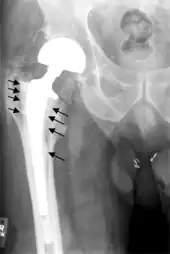

Hip prosthesis displaying aseptic loosening (arrows)

On radiography, it is normal to see thin radiolucent areas of less than 2 mm around hip prosthesis components, or between a cement mantle and bone. These may indicate loosening of the prosthesis if they are new or changing, while areas greater than 2 mm may be harmless if they are stable.[31] The most important prognostic factors of cemented cups are absence of radiolucent lines in DeLee and Charnley zone I, as well as adequate cement mantle thickness.[32] In the first year after insertion of uncemented femoral stems, it is normal to have mild subsidence (less than 10 mm).[31] The direct anterior approach has been shown to itself be a risk factor for early femoral component loosening.[33][34][35]